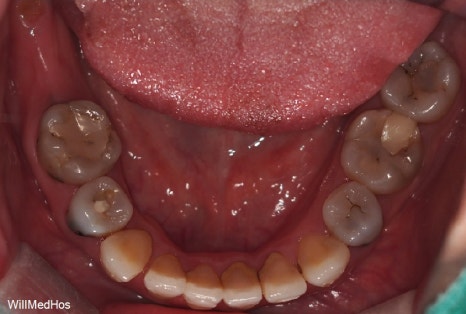

먼저 구강 사진 부터 보도록 하겠습니다.

이미 충치들과 염증으로 인해 치관을 다 없어지고 잔존 뿌리들만 겨우 남아있는 상태들의 치아들

염증으로 인하여 살리기 힘든 치아들도 다수 있었습니다